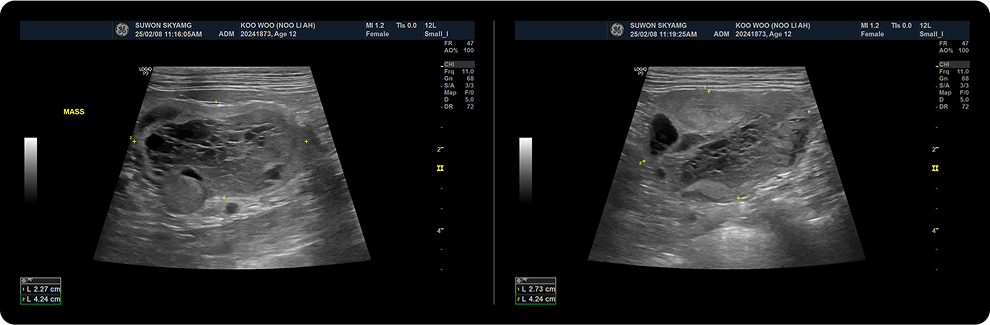

· 초음파 검사

간 실질의 변성과 비대 정도를 평가하고, 쿠싱 질환이 있는 환자에서 호발하는 담낭 병변, 부신의 크기와 형태, 부신 비대, 형태적인 변화, 종양성 변화를 확인합니다.